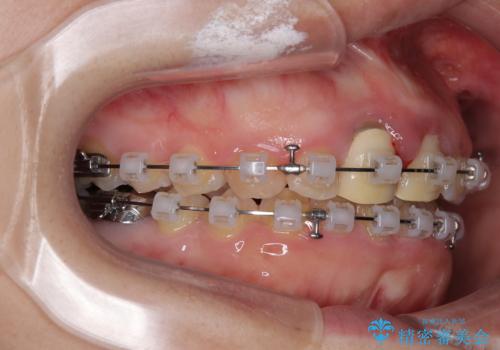

- クリアブラケット

マウスピース装着は煩わしいとのことで、表側のワイヤー装置にて矯正治療を行うこととしました。

前歯のクラウンは、歯肉内深くに削り込まれており、歯肉の炎症が継続していたため、矯正治療後に歯周外科処置を行い、歯肉の腫れを改善させました。